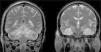

Presentamos el caso de un varón de 38 años con antecedentes de esquizofrenia paranoide que ingresó en nuestro hospital tras ser encontrado inconsciente en un coche cerrado, inhalando el humo del tubo de escape, junto a 2 blíster vacios de benzodiacepinas. A la exploración inicial destacaba baja saturación de oxígeno y un Glasgow de 3. Los valores de carboxihemoglobina eran del 23%. Se realizó una TAC de cráneo inicial (fig. 1) que mostró hipodensidades difusas en hemisferios cerebelosos, sustancia blanca temporobasal bilateral y ganglios basales. Tras una mejora inicial durante las primeras 48h, en las cuales el paciente alcanzó un Glasgow de 10, presentó un empeoramiento clínico con imágenes en TAC de cráneo de severa dilatación de ventrículos laterales y tercer ventrículo, compatible con hidrocefalia obstructiva, por lo que precisó válvula de derivación externa. Posteriormente, en una RMN craneal de control (fig. 2) se comprobó la resolución de la hidrocefalia. Persistían lesiones bihemisféricas que afectaban de manera extensa a sistema límbico, hipocampo, fórnix y áreas temporobasales, lóbulos frontales y parietales y también a ambos hemisferios cerebelosos, todo ello compatible con lesiones anóxico-isquémicas bilaterales múltiples secundarias a intoxicación por CO. Superada la fase aguda, el paciente persistía con deterioro severo de funciones corticales asociado a ataxia de la marcha y síndrome acinético-rígido hemicorporal, sin evidencia de mejoría.

RMN craneal. Corte coronal de RMN cerebral potenciada en T2 que muestra lesiones anóxico-isquémicas múltiples de carácter subagudo-precoz. Las lesiones afectan de manera extensa a ambos sistemas límbicos, hipocampos, fórnices y áreas temporales basales. Pequeñas zonas parcheadas en lóbulos frontales y parietales. Extensas lesiones en ambos hemisferios cerebelosos. Catéter de derivación ventricular en VL derecho.

Las pruebas de imagen, en especial la RMN craneal, han demostrado ser unas técnicas muy sensible para detectar anormalidades cerebrales tras una intoxicación por CO1,9, aportando información sobre las características y el alcance de la lesión producida, correlacionándose mejor que otros parámetros clínicos o analíticos con la evolución del paciente a corto y largo plazo. Aunque inicialmente la RMN puede ser normal1, lo más común es que detecte hiperintensidades en secuencias potenciadas en T210. Las áreas más frecuentemente afectadas son las regiones del cerebro con mayor contenido en hierro (lo que condiciona mayor afinidad de la carboxihemoglobina por ellas) como son los ganglios basales, especialmente el globo pálido, y la sustancia negra. La sustancia blanca periventricular, sustancia blanca subcortical del lóbulo temporal, incluyendo hipocampo, tálamo y cerebelo, también pueden verse afectadas por la toxicidad del CO1,4,9. Nuestro paciente presentaba una extensa afectación tanto supra como infratentorial, con evolución neurológica devastadora.